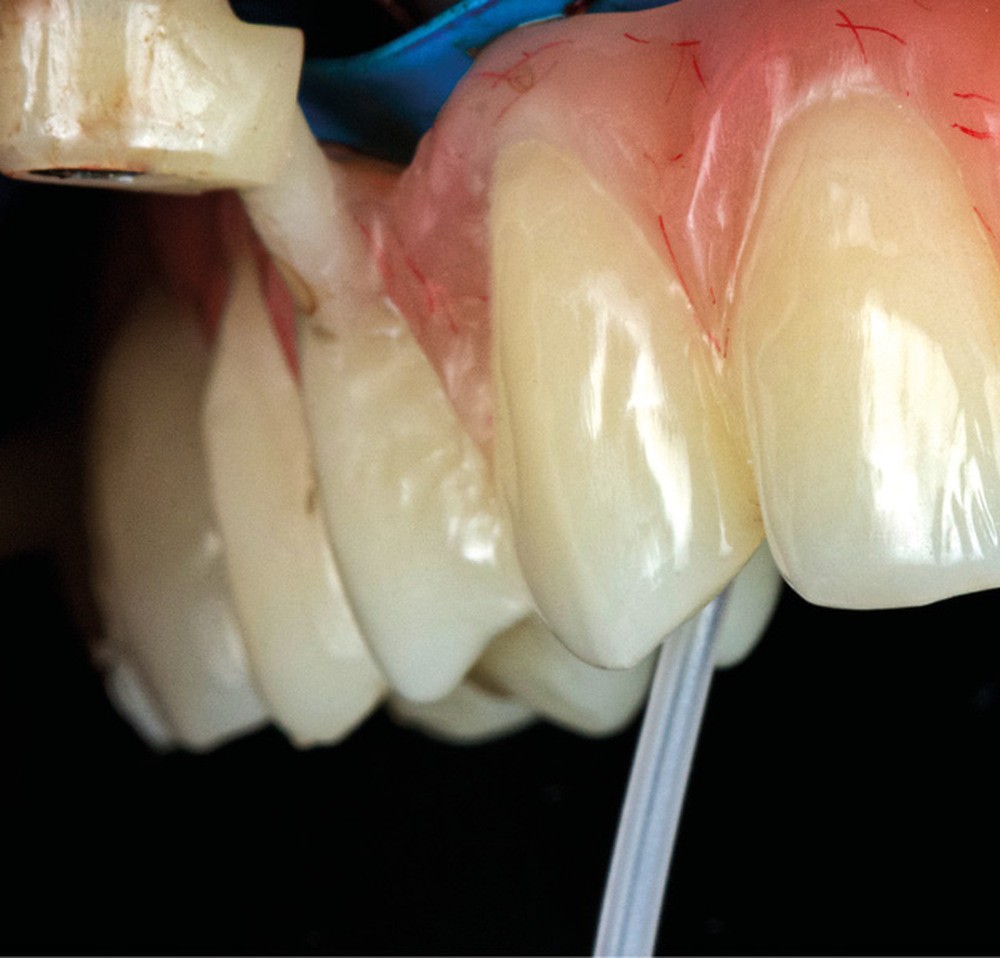

La première étape du protocole des guides à étages (Your3DGuide) est la connexion du guide de positionnement à appui dentaire à la base crâniale métallique hors de la bouche (fig. 4). Cette dernière sera fixée à l’aide de vis transmuqueuses vestibulaires et palatines (fig. 5). Nous avons choisi ce système car la base titane est frittée par laser, ce qui lui conférerait une précision d’adaptation et une rigidité supérieure à une base résine tout en conservant une faible épaisseur. Sur cette base vont se visser les autres étages assurant une stabilisation et évitant un éventuel mouvement lors du forage (et lors de la solidarisation du provisoire).